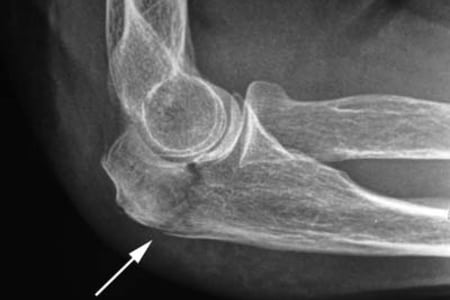

Травмы

Внутрисуставной перелом или перелом кости плеча не заметить невозможно, как и вывих. Возникающая боль настолько острая, что человек теряет сознание. Перелом чаще происходит во время занятий активными видами спорта — футболом, гандболом, легкой атлетикой. Резкая боль является симптомом также полного или частичного разрыва мышц, связок или сухожилий, в обиходе называемого растяжением. Для восстановления целости этих структур могут применяться как консервативные методы лечения, так и хирургическое вмешательство.